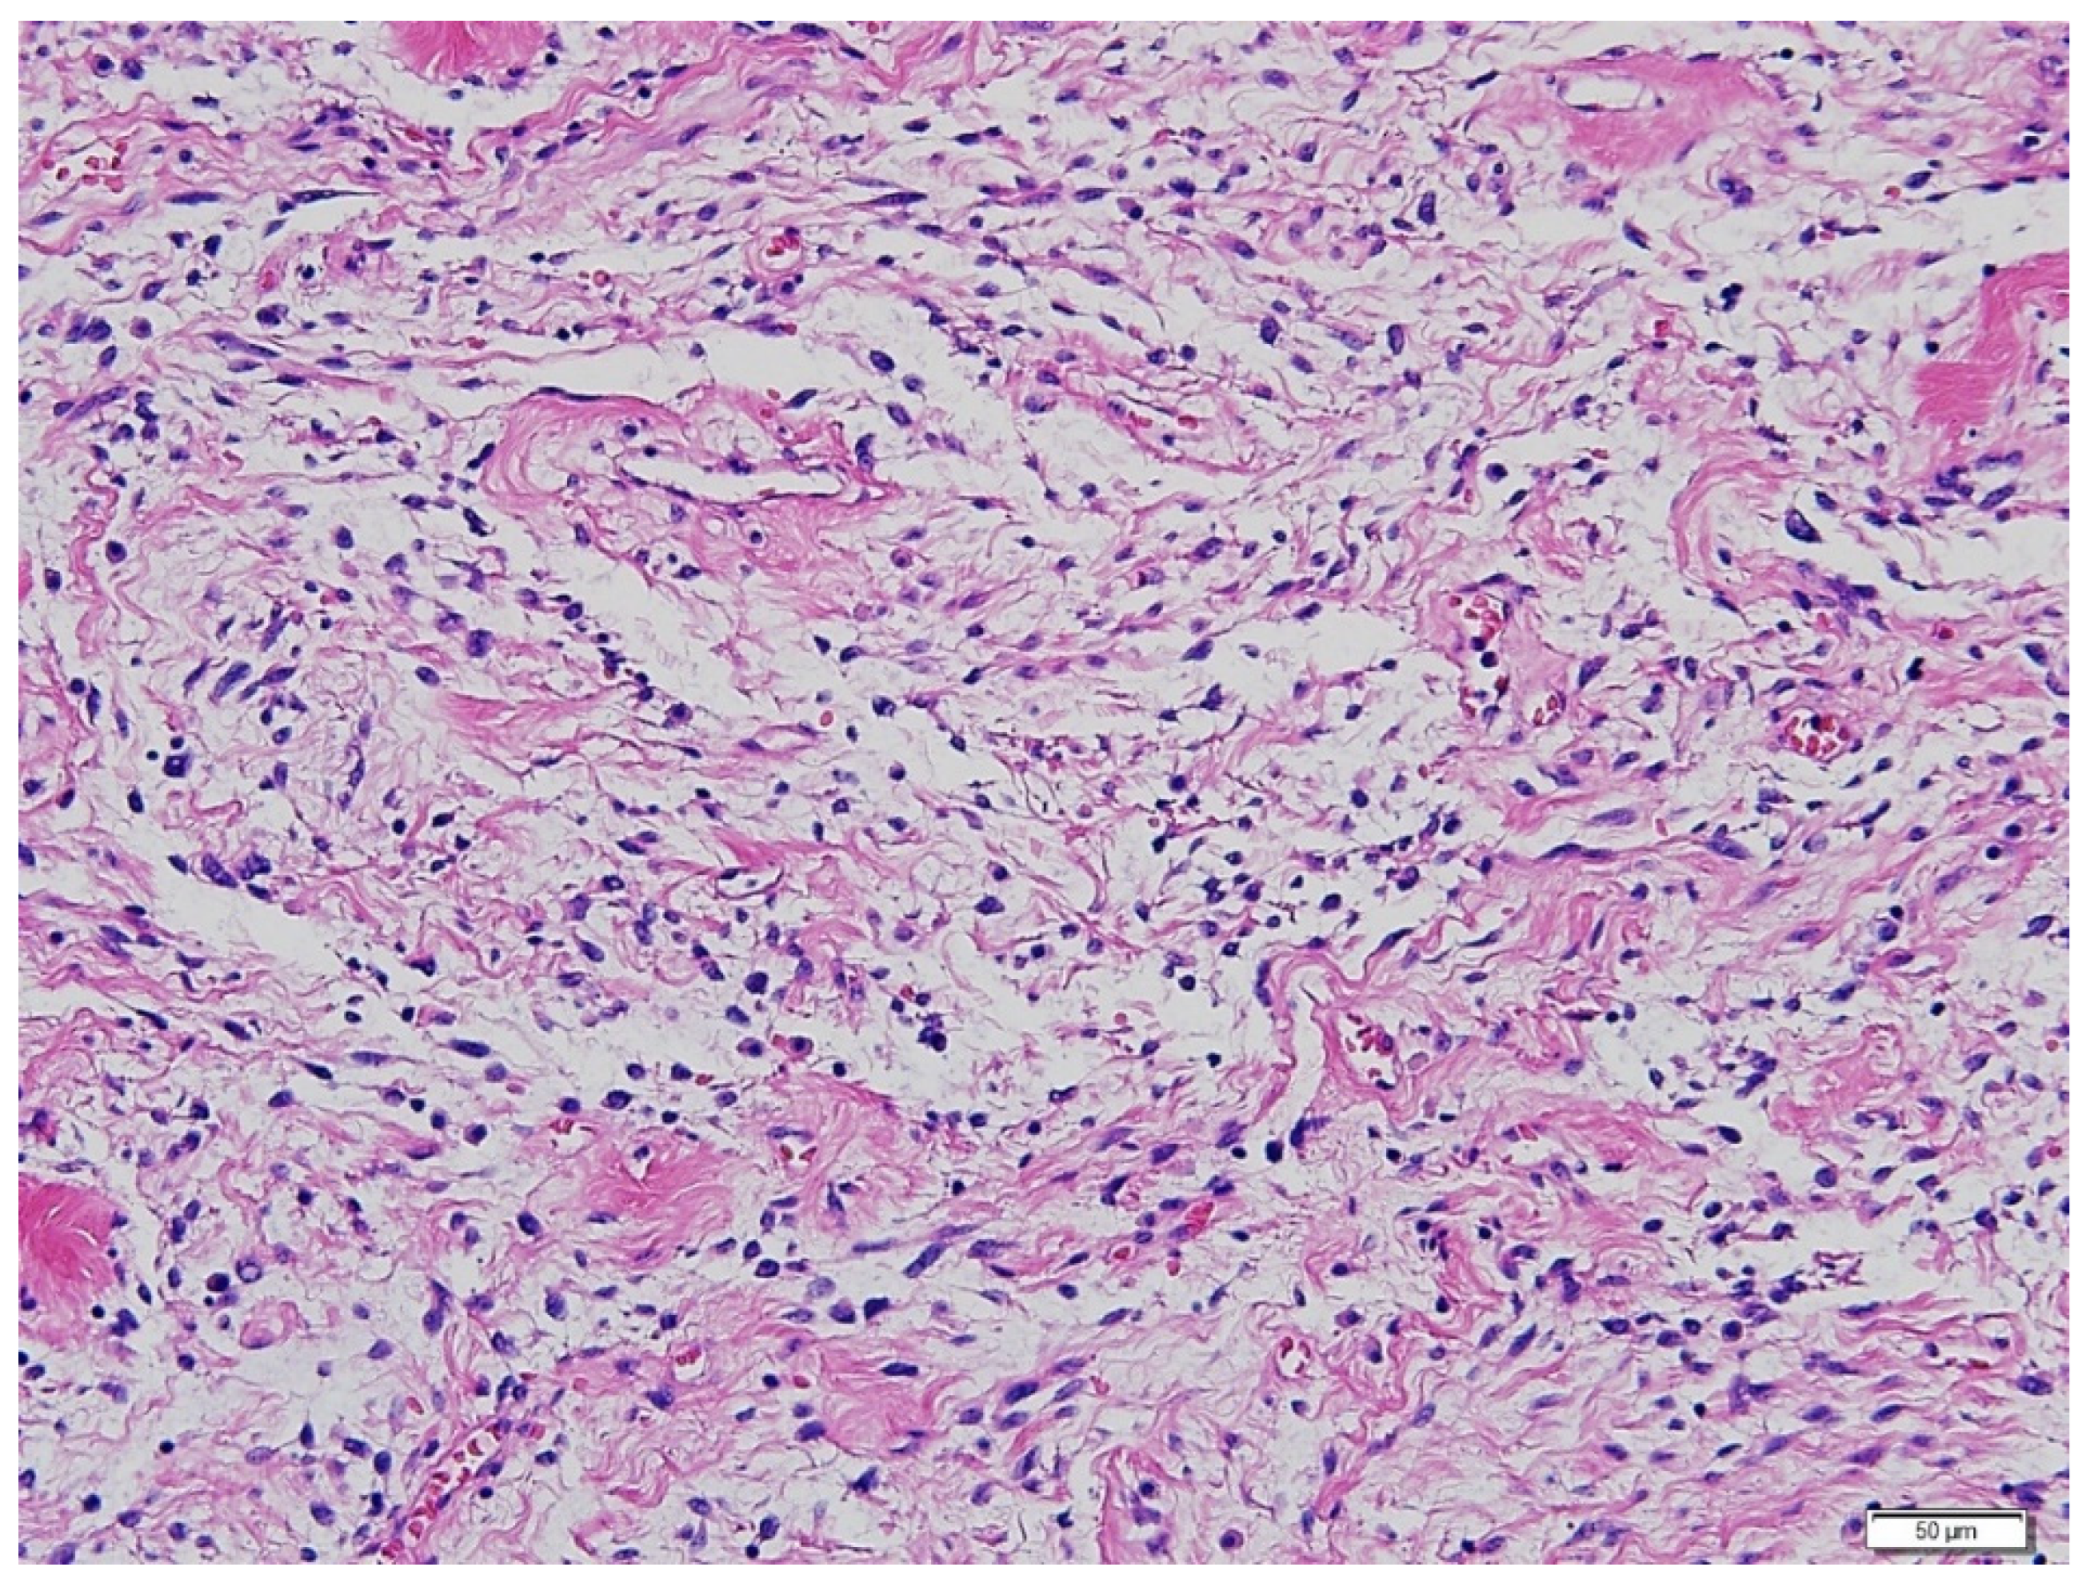

The size and distribution of the pulmonary masses were aggravated along with cystic changes. Considering the rapid growth in a relatively short time and associated distressing symptoms, the decision was made to initiate active antitumor treatment instead of continuing with conservative management and close observation. The patient had previously undergone bilateral salpingo-oophorectomy and was menopausal. Therefore, letrozole, an aromatase inhibitor, was initiated at 2.5 mg once daily. At this time, considering the patient’s aggressive and rapid clinical progression, which was not considered benign, the possibility of malignancy, rather than BML, was raised. Therefore, it was decided to review the surgical specimens of the lung and pelvic masses from 2017. Microscopic examination revealed that the metastatic lung nodules were small, uniform, characterized by bland tumor cells with spindled nuclei and scant cytoplasm, in the background of rich small arterioles or capillary networks (Figure 3). Mitotic counts were up to 1 per high-power field. Necrosis was not present.

Figure 3.

Hematoxylin-eosin staining of the lung mass. Microscopic examination revealed metastatic lung nodules with small, uniform, and bland tumor cells with spindled nuclei and scant cytoplasm, in the background of rich small arterioles or capillary networks. (Magnification 200×).